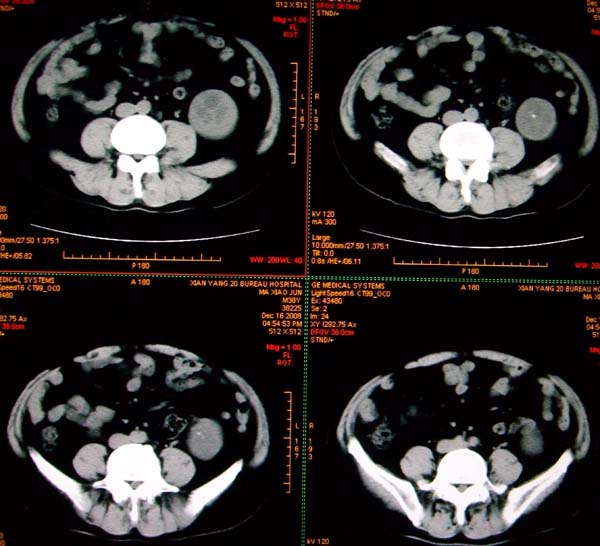

标题: CT17174:M38Y,体检超声提示右肾发育不良,病人无明显不适 [打印本页]

标题: CT17174:M38Y,体检超声提示右肾发育不良,病人无明显不适

右肾发育不良;考虑左肾下极血管平滑肌脂肪瘤可能,建议增强。

右肾微小发育不良  左肾下极错构可能

1)左肾下极占位性病变,不排除肾癌可能;建议行进一步检查。2)右肾发育不良。

左肾下极占位性病变,不排除肾癌可能;建议增强及明确内部组织ct值。右肾发育不良。

右肾发育不良。左肾下极占位。

右肾发育不良。左肾代偿。左肾下极占位,性质待定,建议强化。

右肾发育不良。左肾下极占位。建议增强!

右肾发育不良。左肾下极囊实性占位,建议增强。